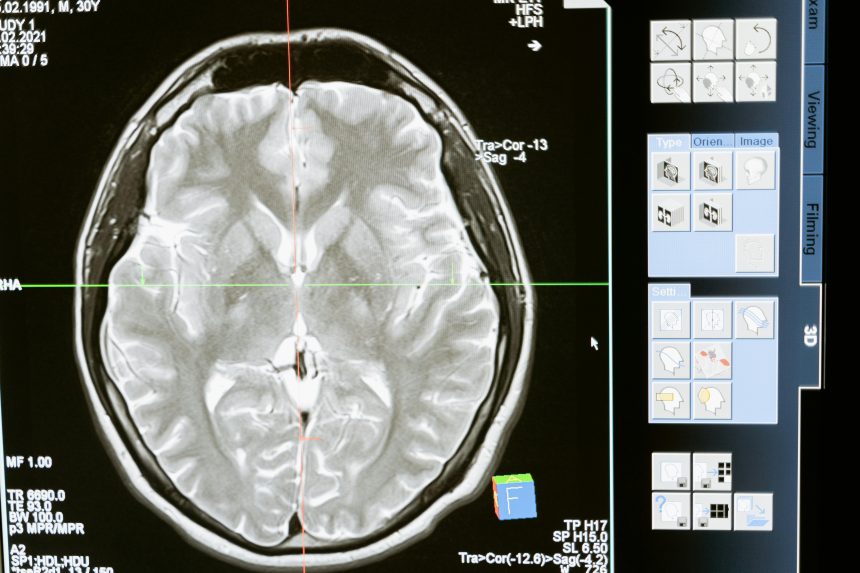

Diagnosis begins in the emergency department and continues during hospitalization. Doctors may use:

- CT scans to quickly identify bleeding, fractures, or swelling

- MRI scans to detect subtle or diffuse damage